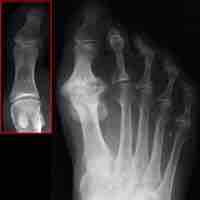

Development of Joints

Movable joints are formed at the intersection of bones and are covered by cartilage, which allows the joint to move freely.

Joints and Aging

Aging is a common cause of chronic joint pain, as wear and tear on the joints from use results in inflammation and osteoarthritis.